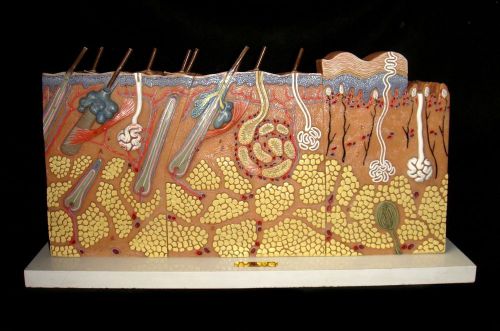

Vintage SOMSO KS3 Block Section of Skin Anatomical Model KS 3